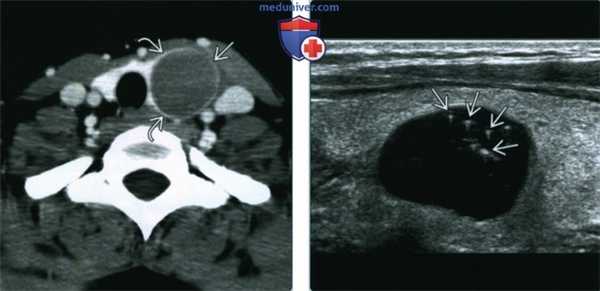

(Слева) КТ с КУ, аксиальная проекция. Округлое образование низкой плотности с четкими контурами, расположенное в левой доле щитовидной железы. Ткань щитовидной железы «окружает» переднюю и заднюю поверхности образования. Пункционная биопсия показала наличие коллоидной кисты с кровоизлиянием.

(Справа) УЗИ, продольная проекция. Типичный коллоидный узел с множественными характерными эхопенными участкам и артефактами по типу «хвоста кометы». Содержимое кисты представлено коллоидными частицами в вязкой жидкости, содержащей тиреоглобулин.